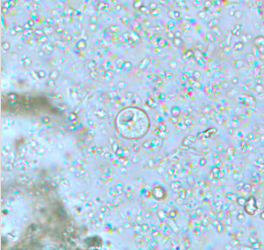

*Entamoeba histolytica*

Cyst